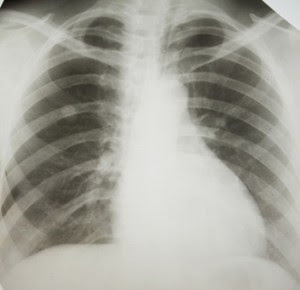

Malignant mesothelioma is a rare type of cancer that occurs in the thin layer of cells lining the body's internal organs, known as the mesothelium. There are three recognized types of mesothelioma. Pleural mesothelioma is the most common form of the disease, accounting for roughly 70% of cases, and occurs in the lining of the lung known as the pleura. Peritoneal mesothelioma occurs in the lining of the abdominal cavity, known as the peritoneum and pericardial mesothelioma originates in the pericardium, which lines the heart.

An individual may be at risk to develop mesothelioma if he or she was exposed to asbestos in the workplace or at home. Mesothelioma is caused by exposure to asbestos and the inhalation of asbestos particles. In most cases, mesothelioma symptoms will not appear in an individual exposed to asbestos until many years after the exposure has occurred. Those with a past asbestos exposure history experiencing symptoms should consult a physician with experience in accurately diagnosing mesothelioma. The earlier mesothelioma is diagnosed, the more likely it is to be caught at an early stage. At earlier stages of mesothelioma progression, more treatment options are available and oftentimes a better prognosis is given. Additional mesothelioma information and statistics can be found in this section.